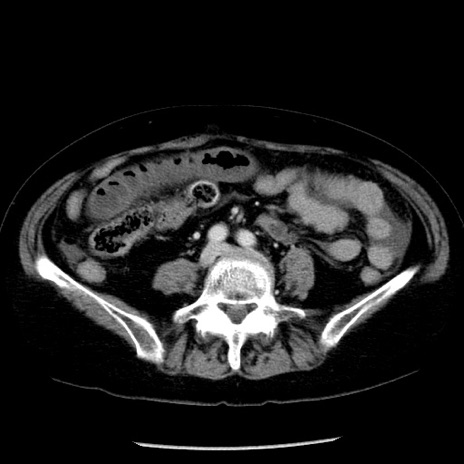

冠状断像

症例13(横断像)

【症例】70歳代女性

【主訴】腹痛、嘔吐

【現病歴】15時間程前(昨晩)より腹痛あり。今朝になっても症状の改善なく、嘔吐あり。腹痛も増悪あり、救急外来受診。

【既往歴】子宮癌全摘術後

【身体所見】意識清明、BP 121/72mmHg、P 74bpm、SpO2 100%(RA)、腹部:平坦・軟、腸雑音ほぼ聴取せず。下腹部・心窩部・臍左上に圧痛あり。反跳痛なし。

【データ】WBC 10600、CRP 0.15